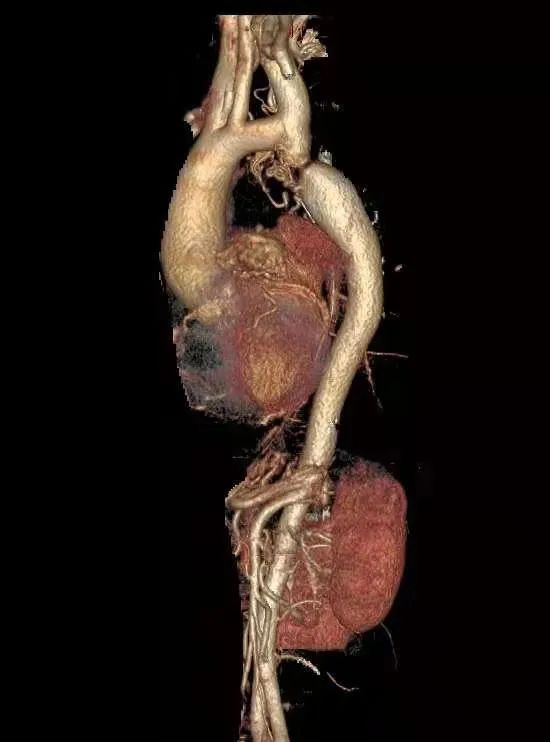

术后主动脉CTA证实主动脉弓离断

主动脉弓离断是一种罕见的先天血管发育变异,通常在幼儿时期通过彩超等检查被发现,主动脉弓离断的患儿死亡率极高,通常死于充血性心力衰竭。本例患者能存活至59岁,考虑跟异常丰富的侧支循环形成有关。在我院副院长、神经内科主任何锦照的指导下,神经内科介入团队于2021年在国际期刊上报道了国际第1例主动脉弓离断出现颅脑大血管闭塞急性脑梗死行急诊取栓治疗的病例,在国际神经介入学术领域发出了河源声音。